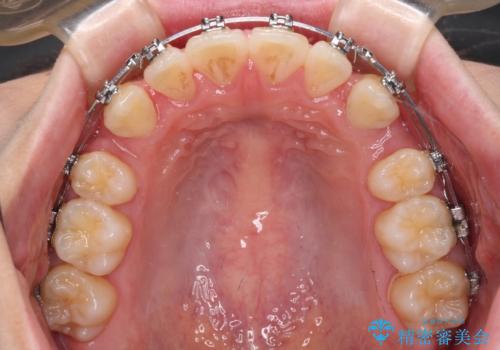

- メタルブラケット

- 1年9ヶ月

上下ともに歯列が前方に突出していたため、上下左右の第一小臼歯4本を抜去し、ワイヤー装置による矯正治療を行うこととしました。

上下左右4本抜歯する場合には、通常2年から2年半ほどの期間を要しますが、舌のトレーニングをしっかりと行っていただいたことで、1年9ヶ月で終了することができました。